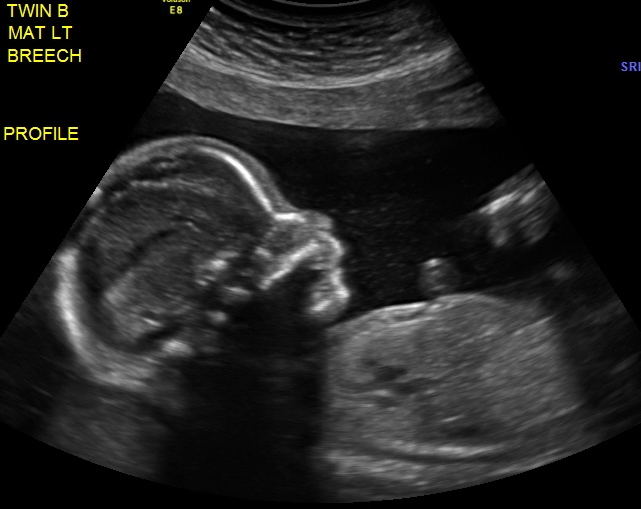

Updates? We had our first BPP done last week @ 32w1d - and both babies looked great - but the most exciting part was that Baby B (who has been breech since around 20 weeks) FLIPPED and now both are head down!!!!!! Looking back I know when it happened - and it was around 30w or so. But now my chances of a vaginal delivery are so much better! Although now I am worried that she is going to flip back - but I keep telling myself they are running out of room in there. Both babies were estimated at over 4lbs each too! It's so crazy.